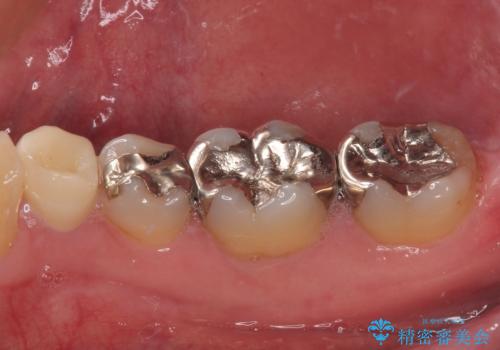

- 右下の銀歯が取れたとのことで来院された患者様です。以前にも取れていたところで、メタルインレーの不適合も認めていたため、次回外れたらオールセラミッククラウンにやり替えていくことを説明していたため、オールセラミッククラウンによる補綴治療を行っていくことにしました。

拡大鏡視野下で虫歯を除去しオールセラミッククラウンに適した形に整えました。

順次、後ろにある不適合のメタルインレーの部位をやり替えていく予定です。